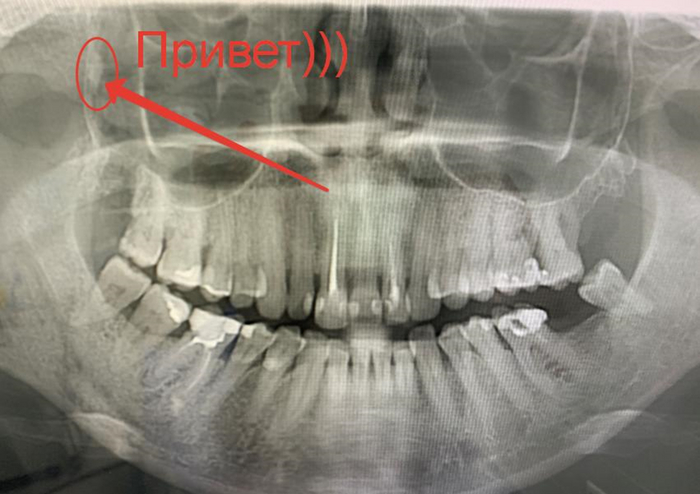

Смотрим на панорамный снимок. 3D-снимок(КТ), к сожалению, не сохранилось, а вот панорамные снимки удалось тогда сфоткать. Верхняя правая восьмерка, корни в раскоряку, близко к Гайморовой пазухе, но таких зубов я удалил, пожалуй, не одну сотню, поэтому протокол уже был отработан.

Далее пробуем подцепить корешок, работаем ювелирно, но он зараза всё-таки улетает в Гайморову пазуху, которая как раз находится над зубом. Сделали контрольный снимок и видим его на задней стенке.